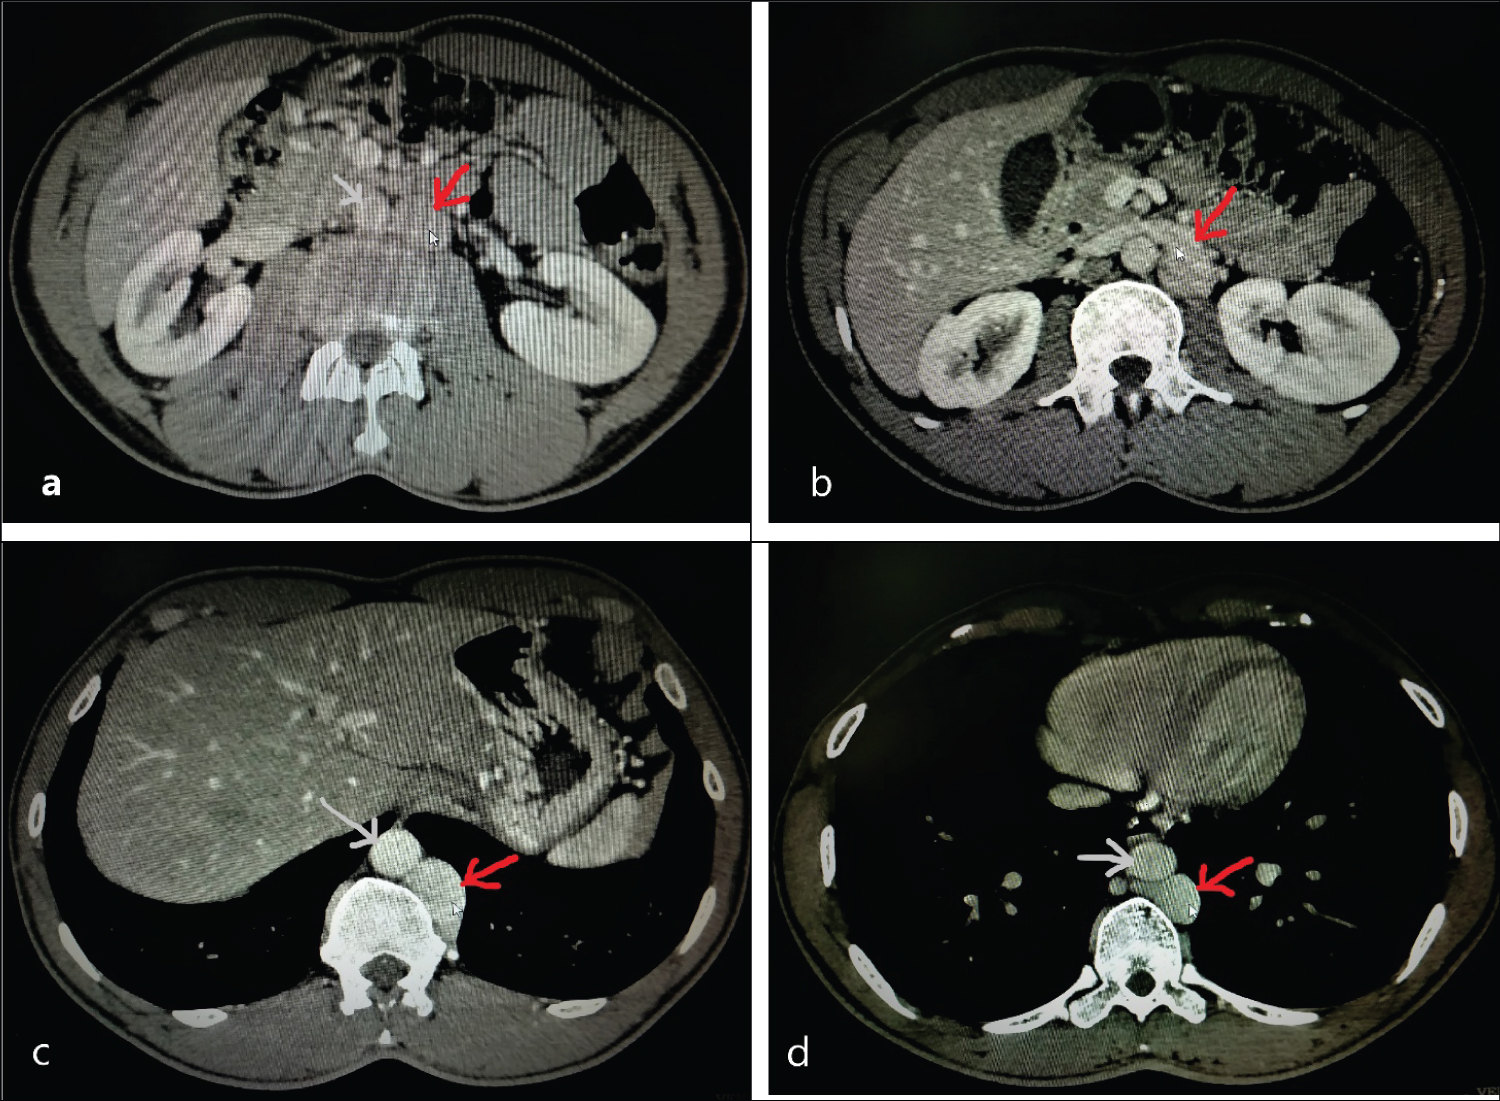

Voluntary kidney donor was a 37 years male. His CT renal Angiography reported right renal vein length of 44 mm and left renal vein length of 28 mm with left side three renal arteries (Figure 1). In view of long right renal vein and single renal artery, preoperative workup was done and he was planned for right laparoscopic donor nephrectomy (LDN). Transperitoneal right LDN was performed with 4 port. After colon mobilisation ureteral gonadal complex was identified and dissected to reach hilum. Hilar dissection was performed after duodenal kocherisation. Single renal artery was dissected till its origin from aorta. Superior dissection of kidney to free it from Adrenal gland was performed. Lateral and posterior dissection done to mobilise kidney completely. Right renal vein and right renal artery was clipped with 10 mm Hem-o-Lok clips. Kidney was retrieved using Pfannenstiel incision. There was no intraoperative complication and surgery was performed as any other right LDN. Measured graft renal vein length was 30 mm and was anastomosed to recipient right external iliac vein (End to side). Postoperative period was uneventful and donor was discharged on 3rd postoperative day. Recipient made a good recovery with serum creatinine of 1.2 mg/dl on 5th postoperative day.

Figure 1: Left sided inferior vena cava. From caudal to cranial (a-d) show left sided inferior vena cava, origin of right renal vein from left inferior vena cava, continuation of left sided inferior vena cava till D10 vertebra further confirming complete left sided inferior vena cava(red arrow- inferior vena cava, grey arrow- aorta). View Figure 1